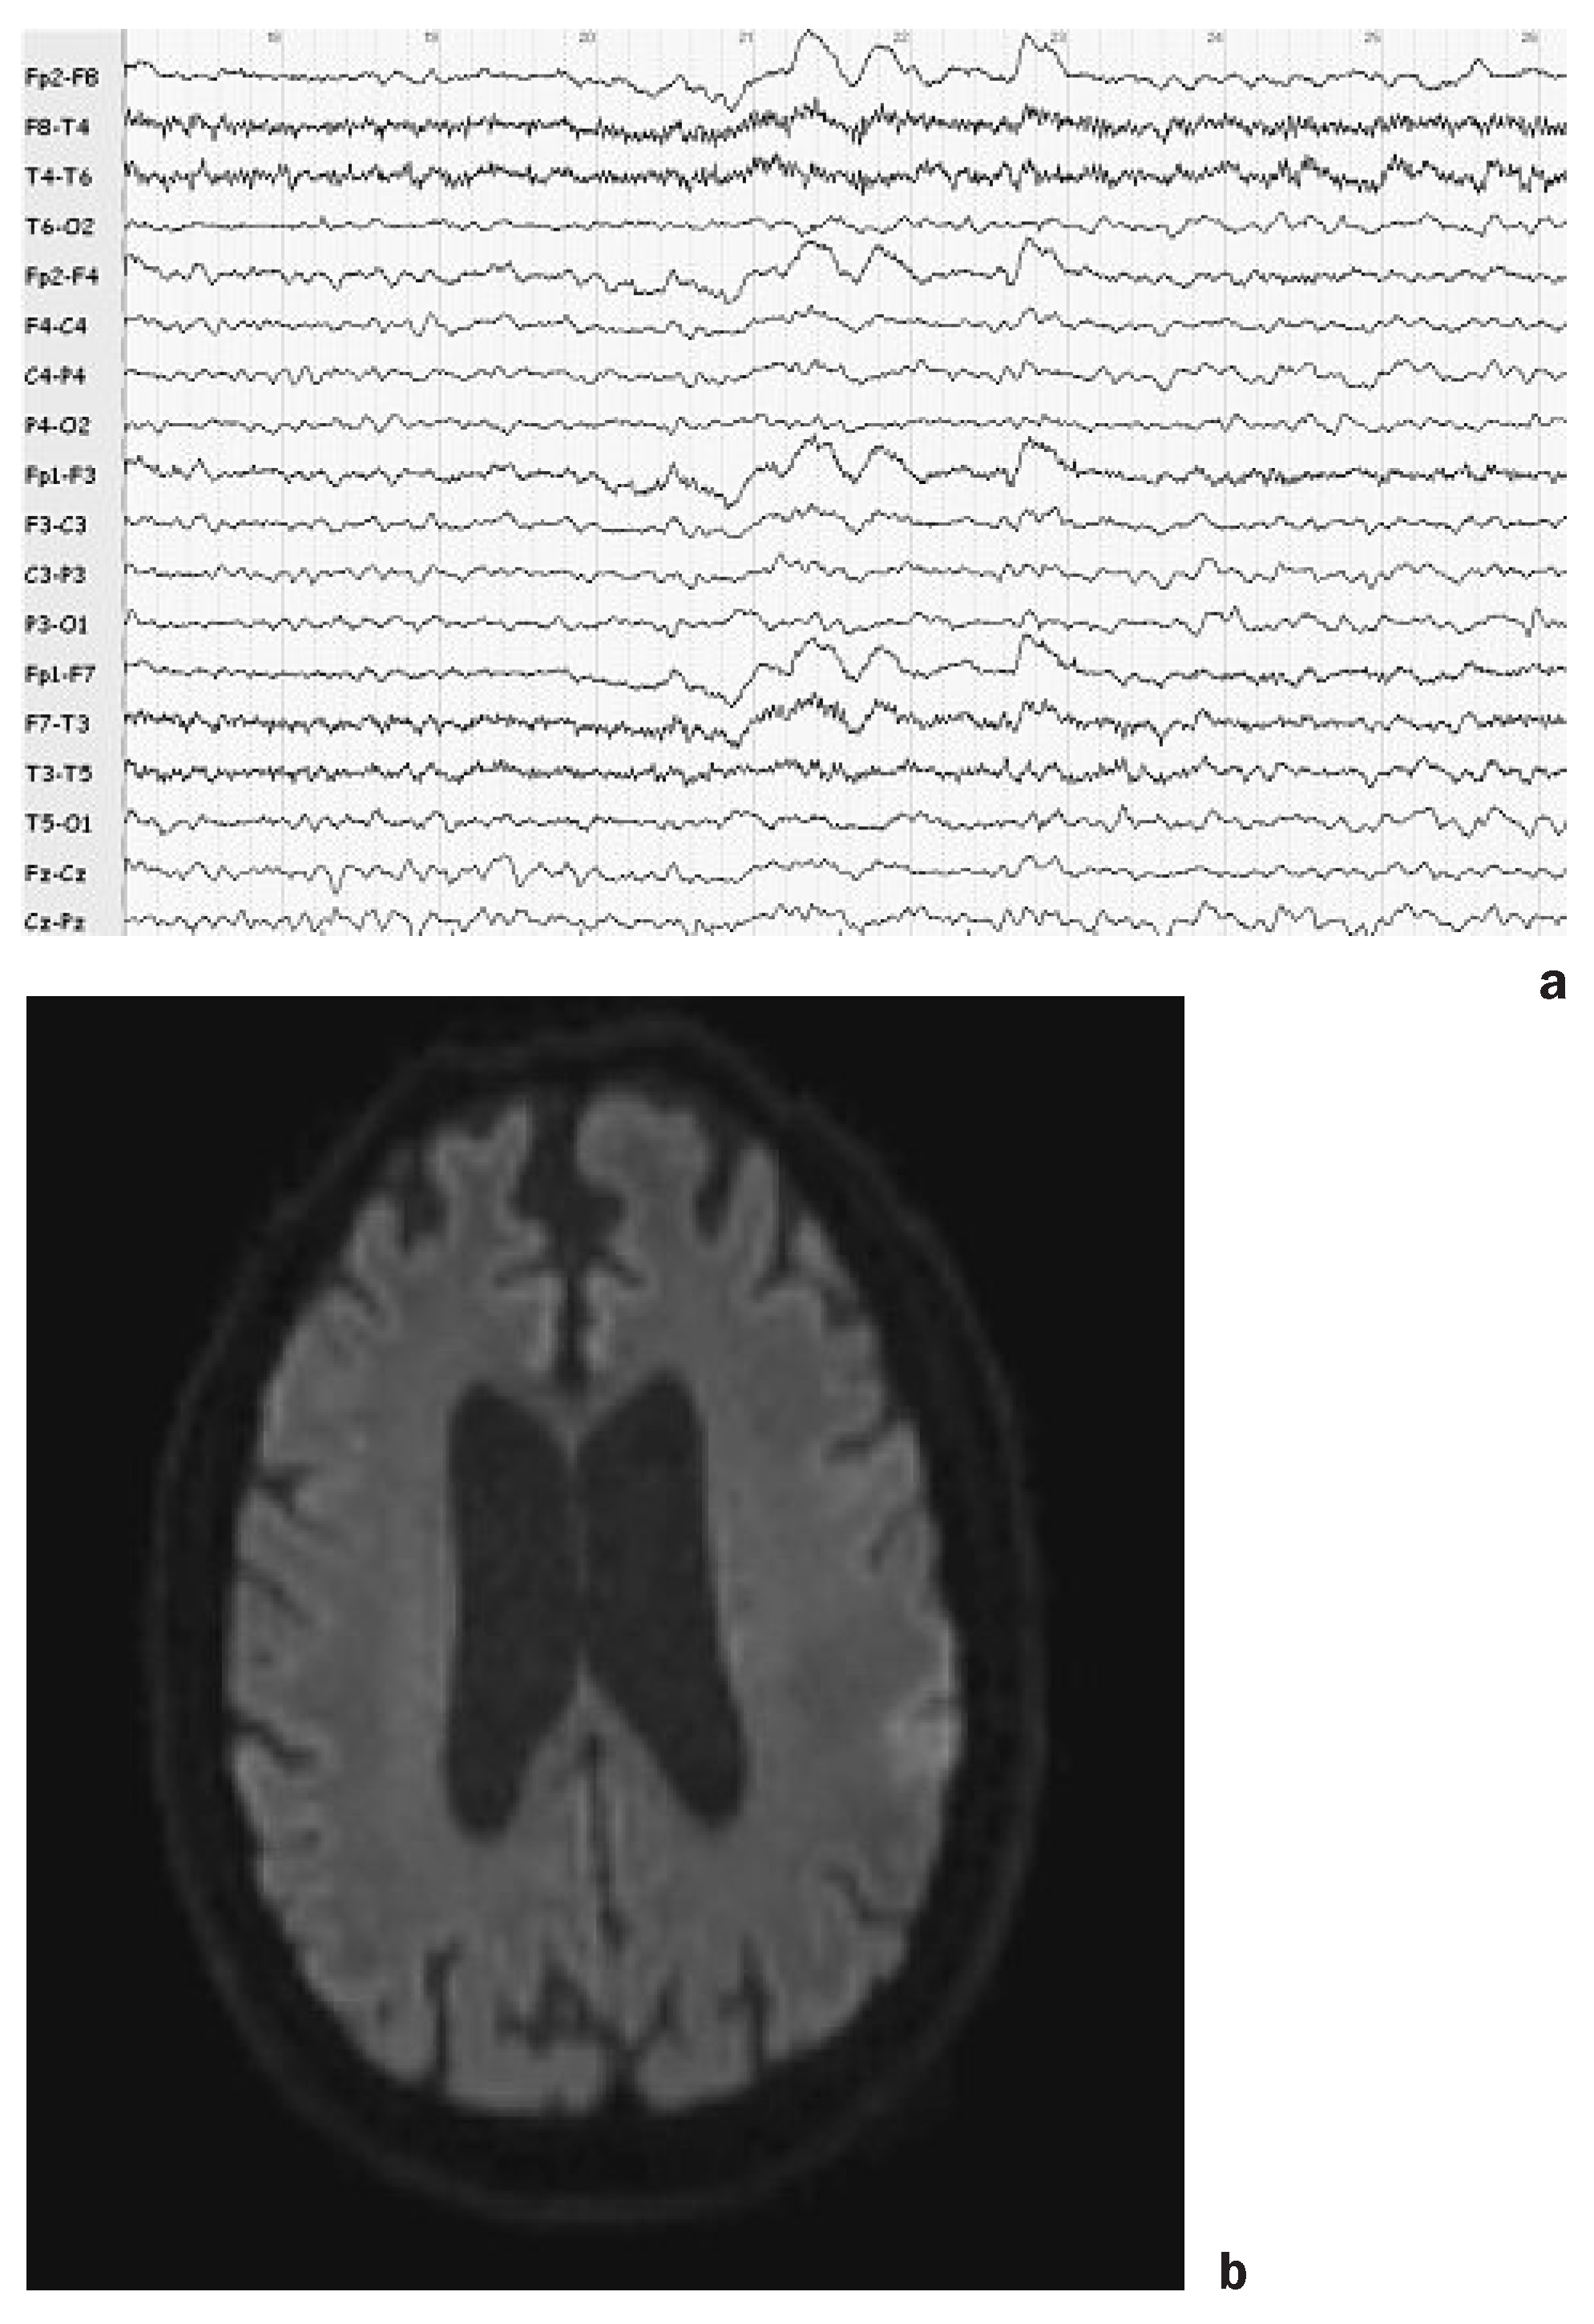

Normal pressure hydrocephalus

- Palm, WM; Saczynski, JS; van der Grond, J; Sigurdsson, S; Kjartansson, O; Jonsson, PV; et al. Ventricular dilation: Association with gait and cognition. Ann Neurol. 2009, 66(4), 485–93. [Google Scholar] [CrossRef] [PubMed]